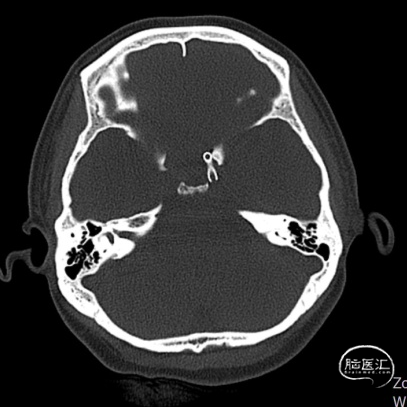

入院后完善多序列MR左侧颈内动脉C4段可见囊状突起、DWI未见新鲜梗死。

左侧颈内动脉造影提示:左侧颈内动脉C4段多发动脉瘤。大小分别为3.5mm*2.5mm、2.5mm*2.5mm,余各血管及其分支血管走形正常,动脉期、毛细血管期、静脉期均未见异常血管病变,脑循环时间正常。

2. 术前全脑血管造影提示:左侧颈内动脉C4段多发动脉瘤;

(A)

(B)

(C)

A:支架到位前造影确定动脉瘤位置以及拟释放支架位置;B:支架到位;C:支架到位后再次确定支架与动脉瘤位置关系。